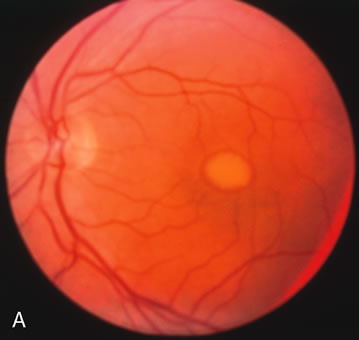

In retinitis pigmentosa (RP), the pigment abnormalities of atrophy, migration, and clumping are made apparent by transmitted hyperfluorescence and blocked hypofluorescence (Fig. 1A). Patients who have very minimal pigmentary alterations (pauci pigmentary RP) or no pigment abnormalities (RP sine pigmento) may show the abnormalities on fluorescien angiography (FA). It is uncommon to see choriocapillaris atrophy except in the late stages. This finding corresponds to the histopathology, which shows that the earliest abnormalities are in the photoreceptors and that the choroid is normal.1

Dye leakage in RP may occur from the retinal vessels or at the level of the retinal pigment epithelium (Fig. 1B).2–4 The leakage may be seen in the macula and posterior pole, along the vascular arcades in the distribution of the radial peripapillary capillaries, and in the periphery (where an exudative vasculopathy resembling Coats' disease is suggested).

Of more clinical importance is the role of FA in the diagnosis and treatment of cystoid macular edema (CME) (Fig. 1C and D). Stereoscopic FA indicates that the leakage, which may be diffuse or have the typical petaloid stellate appearance of CME, can come from the perifoveal retinal capillaries, from the choroid through the RPE, or from a combination of both sources.4 With the recent suggestion that CME in RP may be successfully treated with acetazolamide,5, 6 FA is thus important to document the diagnosis of CME, establish the origin(s) of leakage, and follow patients during and after therapy.